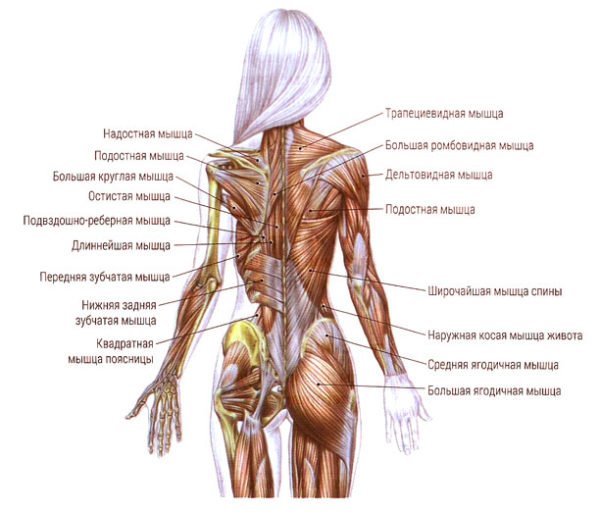

- Цельный позвоночный столб окружает со всех сторон мышечная ткань. Благодаря мышцам удается избежать большинства механических повреждений, которые непременно возникли бы, не будь у позвоночника мышечной защиты. Также ткань уменьшает нагрузку, выпрямляя спину и моделируя работу органов, расположенных внутри тела.

Мышцы спины

Поясничные позвонки наиболее массивные и крупные во всём позвоночнике, с увеличением от первого поясничного к пятому, что объясняется максимальной нагрузкой на нижний отдел позвоночника. Позвонки грудного отдела и крестец малоподвижны, что требует от позвонков поясничного отдела повышенной подвижности. Пять поясничных позвонков человека и крестец образуют пять позвоночно-двигательных сегментов, что обеспечивает принципиальную возможность поворотов корпуса в стороны, движений корпуса в сагиттальной и фронтальной плоскости, а также комбинированные повороты и наклоны. Наличие сильных мышц поясницы помогает осуществлять движения даже с дополнительной нагрузкой.

Центральная ось скелета, позвоночник, формируется 24 позвонками, крестцом и копчиком. Он содержит спинной мозг и спинномозговые нервы. Он связан с тремя блоками: головой, грудной клеткой и тазом, и содержит зоны, которые образуют три последовательных изгиба, видимых в профиль.

Очень сочлененный, он содержит 74 сустава, в т.ч. 23 межпозвоночных диска. Он может поочередно становиться несущей колонной для корпуса, жесткой и прочной, или гибкой и подвижной связью благодаря многочисленным мышцам, которые могут его зафиксировать или заставить двигаться.

Воздействия мышц живота служат либо для того, чтобы зафиксировать позвоночник, либо заставить его двигаться. Они осуществляются на поясничном отделе позвоночника или на его нижнем спинном отделе.